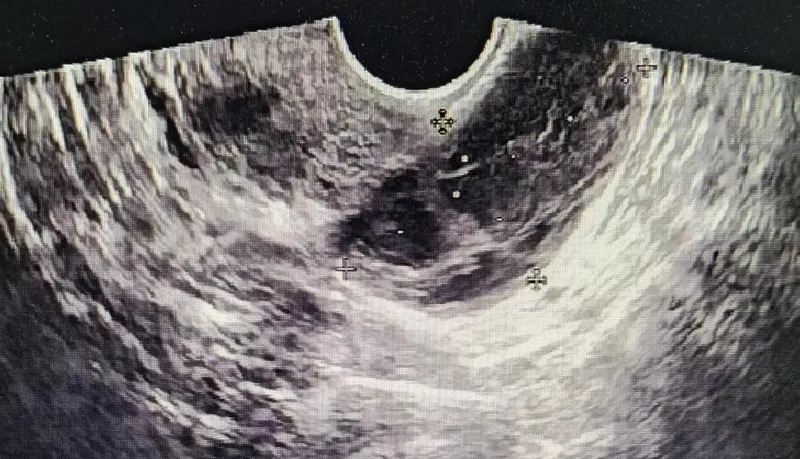

我趕緊為她們

進(jìn)行超聲檢查

屏幕上顯示

患側(cè)附件區(qū)

有囊性包塊

囊內(nèi)透聲差

盆腔內(nèi)有

不規(guī)則的液性暗區(qū)

憑借經(jīng)驗(yàn)

我懷疑這是

黃體破裂